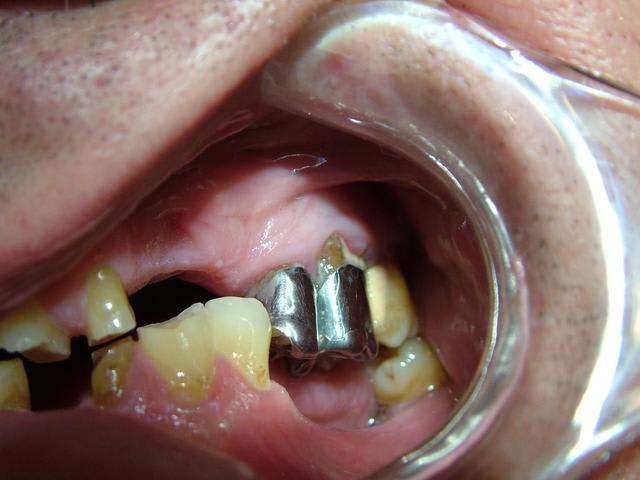

Contrairement à ce qui a été dit...Il n'y a pas de perte de Dimension verticale. Les secteurs posterieurs sont plus ou moins preservés

(couronne métallique..)

> posterieurs sont plus ou moins preservés

> (couronne métallique..)

L'idée de cingulum me semble la plus acceptable car il y a néanmoins un calage postérieur qui a sans doute permis de conserver la DV d'origine ou du moins éviter qu'il y ait un effondrement important. La remarque de cingulum me semble particulièrement pertinente.

Augmenter la DV dans ce cas serait la solution de facilité mais on perdra le seul calage qui parait correct du côté droit, à moins de faire des inlays de surélévation.

Je confirme il y a un calage posterieur...presque pas de perte de DV. Donc la distance "maxillo-mandibulaire" n'a pas diminuée.

Il est vrai que la DV me semble conservé car il y a un calage postérieur côté droit et côté gauche.